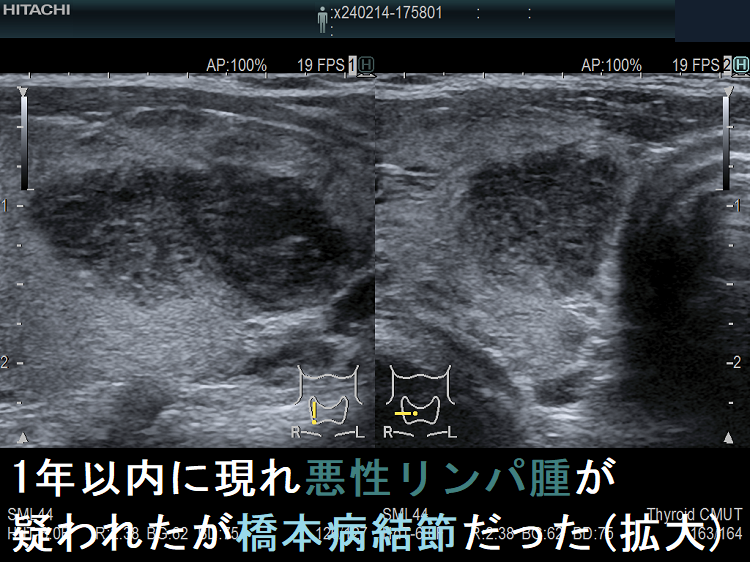

![1年以内に現れ悪性リンパ腫が疑われたが橋本病結節だった 1年前 (水平断)[拡大] 1年以内に現れ悪性リンパ腫が疑われたが橋本病結節だった 1年前 (水平断)[拡大]](../images/special/thyroid2/images20251130213537.png)